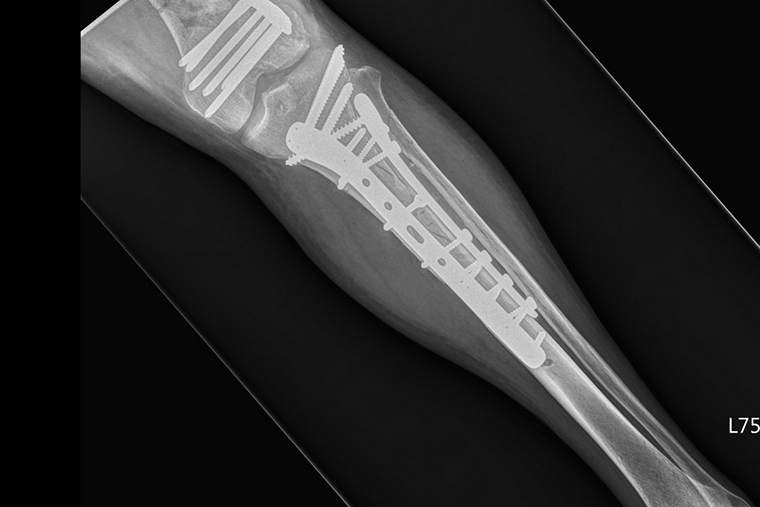

▲醫師採用「開放性復位及內固定手術」,將許先生左側小腿髕骨與脛骨處進行復位固定。(圖/台北慈濟醫院提供)

開放性骨折以「開放性復位及內固定手術」為主要治療方式,李奕澄說明,治療會在麻醉後施行,將骨折的患部皮膚劃開1切口,避開神經血管並拉開肌肉,把斷骨復位至正確位置,再以骨板及骨釘固定斷骨,最後覆蓋石膏作為保護。通常情況下,病人在術後約1個月左右即可拆除石膏,而骨頭癒合速度則要視病人本身情況而定。以許先生為例,多處開放性骨折且情況嚴重,生命跡象雖趨於穩定,但經過多方位的評估後,醫師是採取多次、少範圍的方式進行手術。